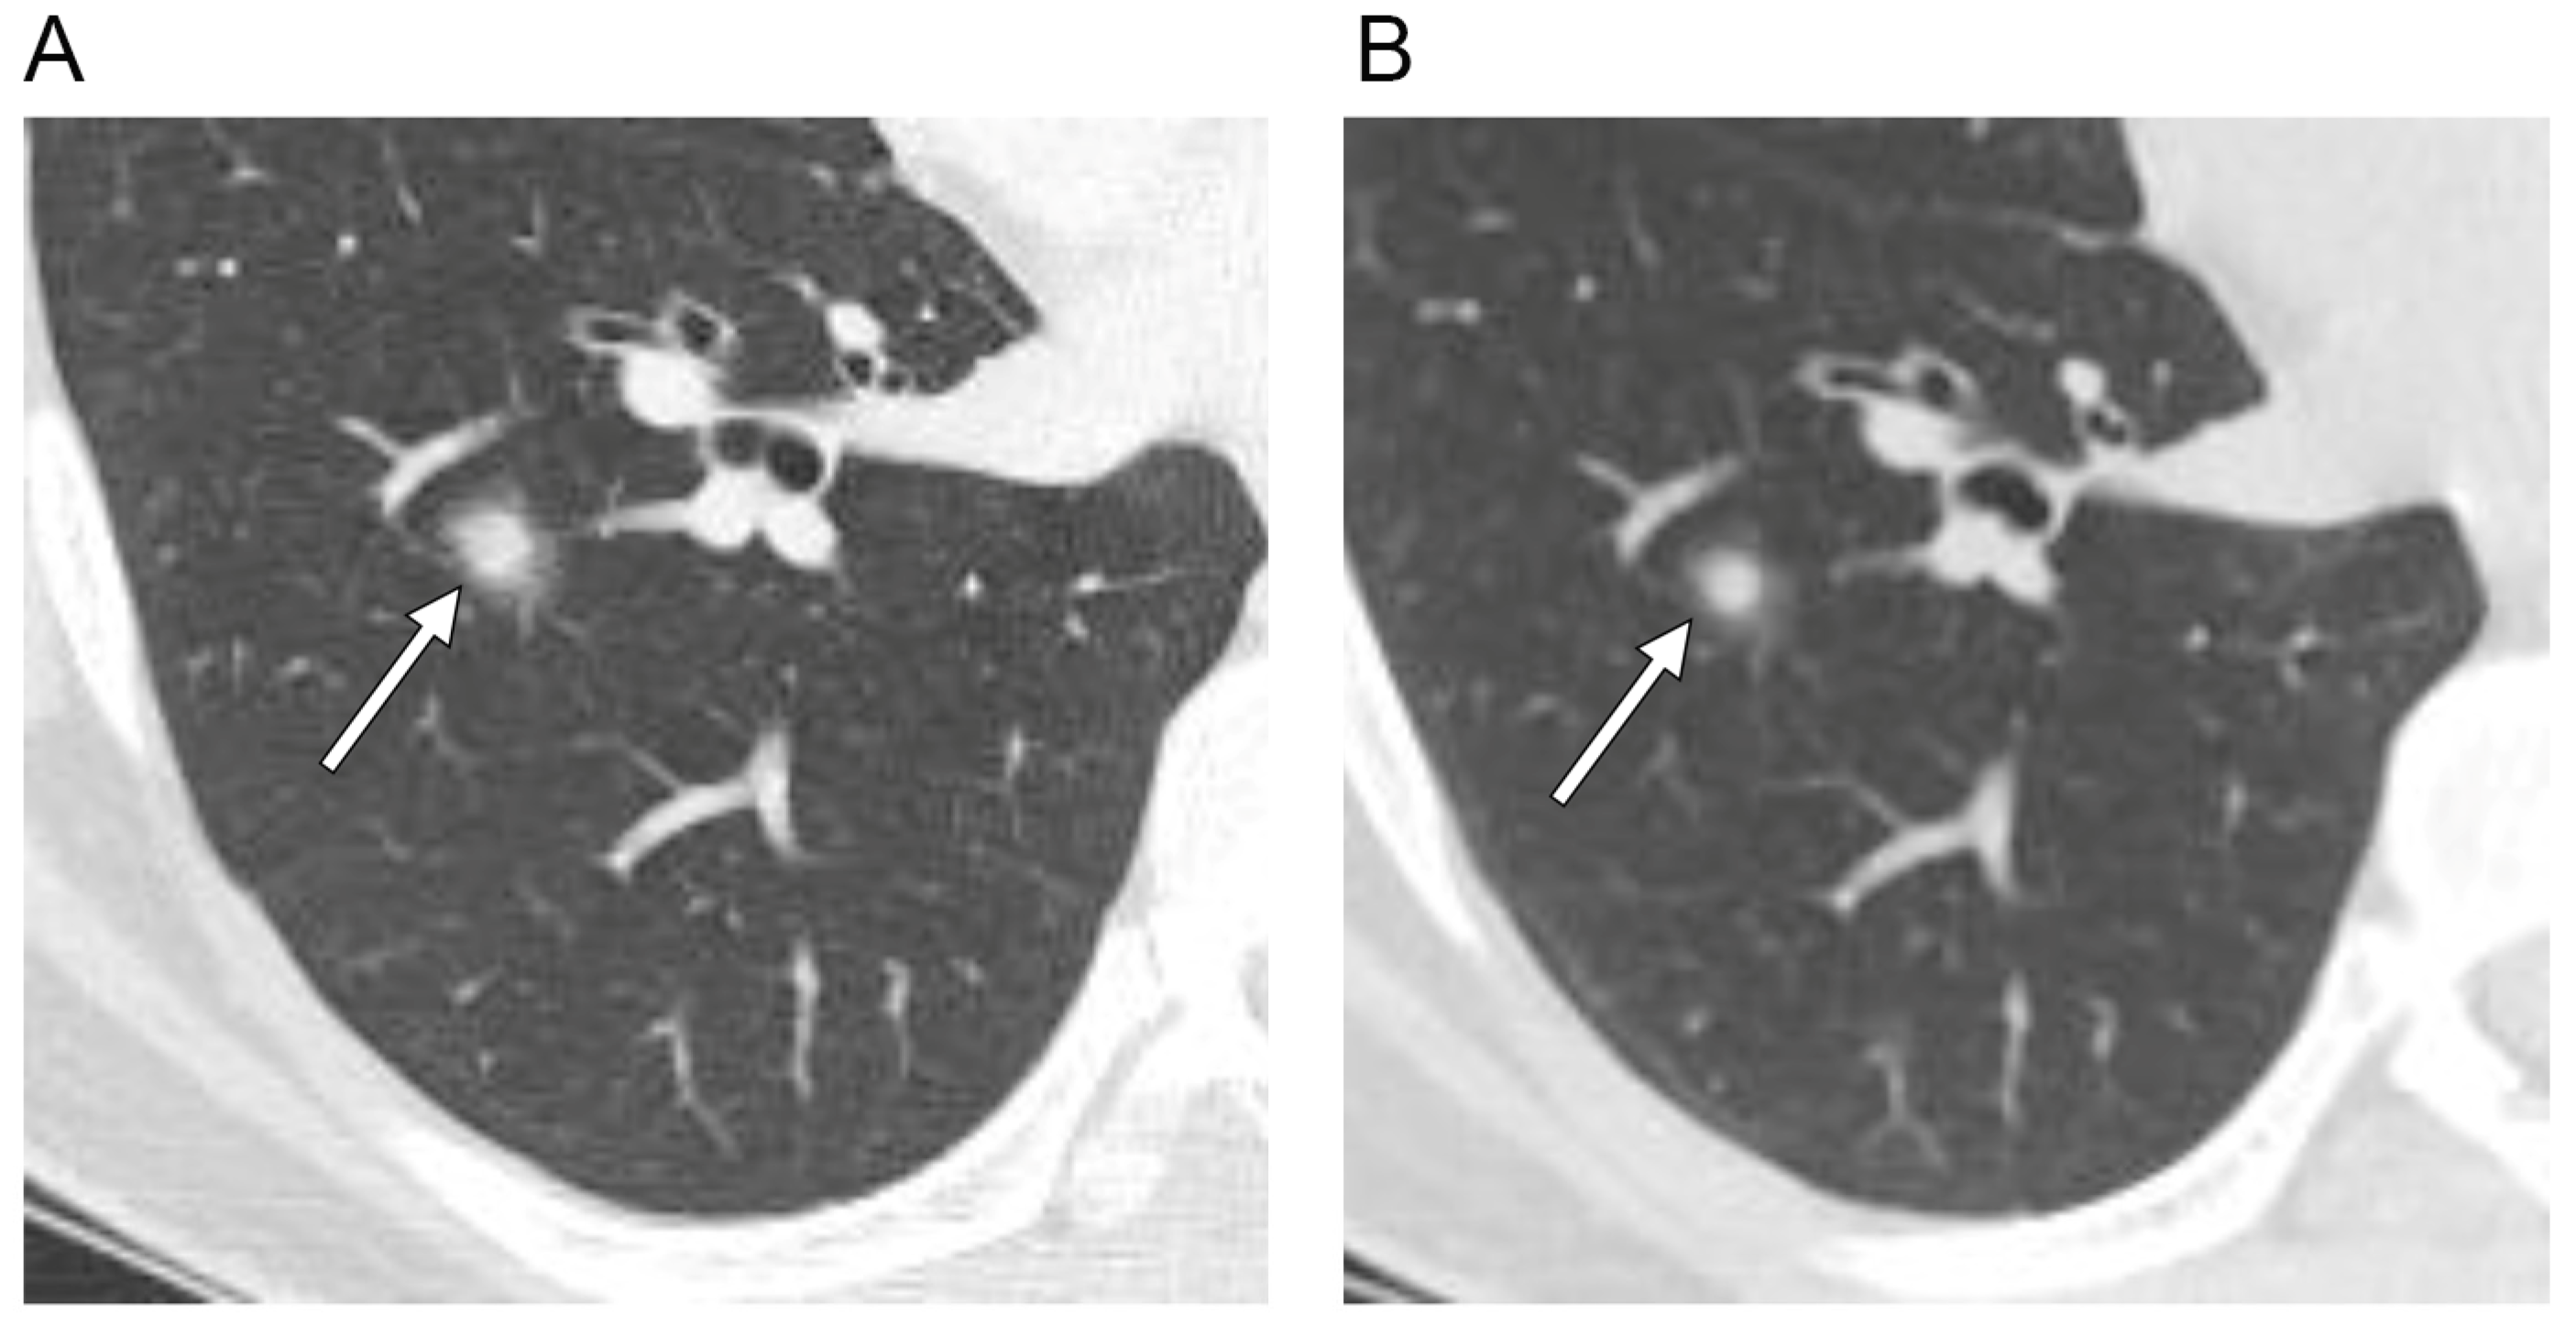

| Perivascular lucency | 2 (12) |